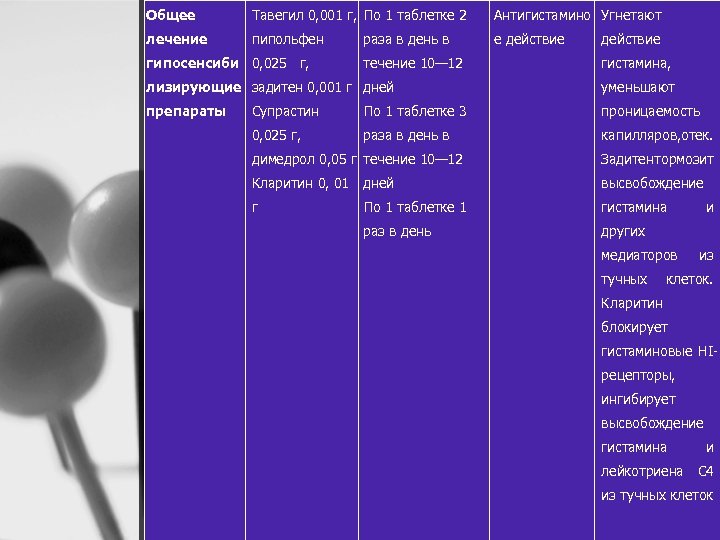

Общее Тавегил 0, 001 г, По 1 таблетке 2 Антигистамино Угнетают лечение пипольфен е действие гипосенсиби 0, 025 г, раза в день в течение 10— 12 действие гистамина, лизирующие задитен 0, 001 г дней уменьшают препараты Супрастин По 1 таблетке 3 проницаемость 0, 025 г, раза в день в капилляров, тек. о димедрол 0, 05 г течение 10— 12 Задитен ормозит т Кларитин 0, 01 дней высвобождение г По 1 таблетке 1 гистамина раз в день других медиаторов тучных и из клеток. Кларитин блокирует гистаминовые HI рецепторы, ингибирует высвобождение гистамина и лейкотриена С 4 из тучных клеток